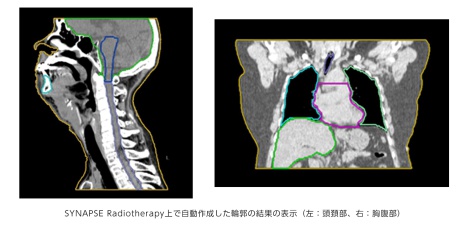

今回発売する放射線治療計画支援ソフトウェア「SYNAPSE Radiotherapy」は、富士フイルムの3次元画像解析システム「SYNAPSE VINCENT(シナプス ヴィンセント)」で培ったノウハウを基にAI技術を活用して開発した「臓器輪郭作成支援機能」と、医用画像情報システム(PACS)で培った技術を活かした「放射線治療ビューア機能」により、医師の放射線治療計画のワークフローを支援します。

放射線治療では、がん細胞の存在する腫瘍部周辺の正常な臓器に影響を及ぼさないように、あらかじめ計画した量の放射線を、決められた位置に正確に照射する必要があります。医師は、治療計画装置上で、治療計画用に撮影したCT画像(計画CT)から、腫瘍部およびその周辺の正常な臓器の輪郭をマークし、腫瘍部の形状や正常な臓器との位置関係によって、放射線の入射方向、照射範囲、投与線量、照射回数などの治療計画を決定します。多数のCT画像一枚一枚から腫瘍部および正常な臓器の輪郭をマークする作業は緻密さと、労力を要します。また、複数回の照射の中で腫瘍部が縮小するなど形が変化した場合などは、途中で治療計画を立て直すこともあり、同様の作業が複数回発生することもあります。近年、治療装置の高度化に伴い、より高精度かつ複雑な治療計画が求められるようになってきていることから、医師の負担はますます大きくなっています。